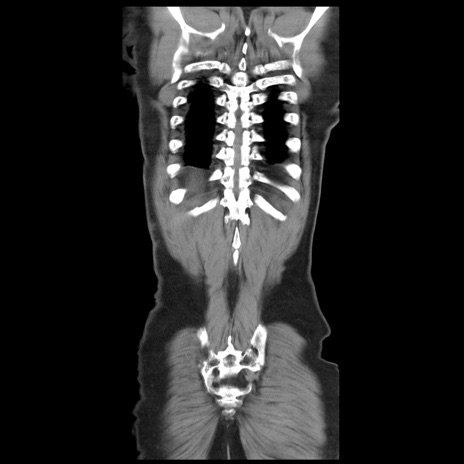

矢状断像